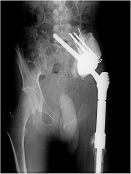

Klasik osteosarkomun cerrahi tedavisi, tümör ve tümör dokusu ile temas etmiş tüm bölgelerin, üzerinde yeterli kalınlıkta sağlıklı doku örtüsü bırakılarak, tümöre dokunulmadan çıkartılmasıdır. Kemoterapi, tümörü küçülterek çıkartılmasını kolaylaştırmak, bölgesel tekrar (lokal nüks) riskini azaltmak ve sistemik yayılmayı (metastaz) engellemek için ameliyat öncesi (neodjuvan) ve ameliyat sonrası (adjuvan) mutlaka uygulanmalıdır. Neoadjuvan kemoterapi ile mikrometastazların önüne geçmeye çalışılır.

Akciğerlerde ortaya çıkabilecek metastazlar kemoterapi ve cerrahi ile tedavi edilirler. Hastalığın tamamen tedavi edilebilme oranı doğru ve başarılı yöntemlerle % 65-70 olarak belirlenmiştir.

Yüksek dereceli kondrosarkomlarda geniş rezeksiyon (negatif cerrahi sınır) ve uygun rekonstrüksiyon yapılmalıdır. Hastaların metastaz ve lokal nüks açısından yakın takibi gerekir.